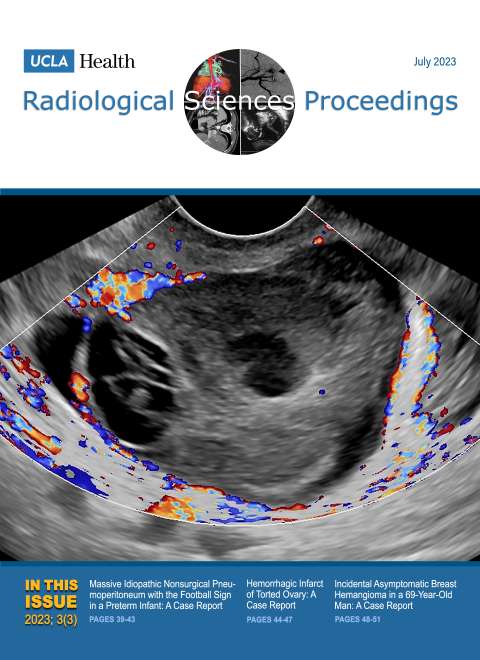

October 2023

Volume 3, Issue 4

- Survey on Management of Unilateral Axillary Lymphadenopathy after Recent Ipsilateral COVID-19 Vaccination

- Primary Pulmonary Anaplastic Large Cell Lymphoma Presenting as Progressive Respiratory Failure in a 38-Year-Old Woman: A Case Report of a Rare Entity

- Kommerell Diverticulum and Agenesis of the Left Common Carotid Artery in a Patient with Dysphagia: A Case Report

- Extensive Subcutaneous Calcinosis and Hypercalcemia in the Setting of Mineral Oil-Injection-Related Foreign Body Reaction: A Case Report